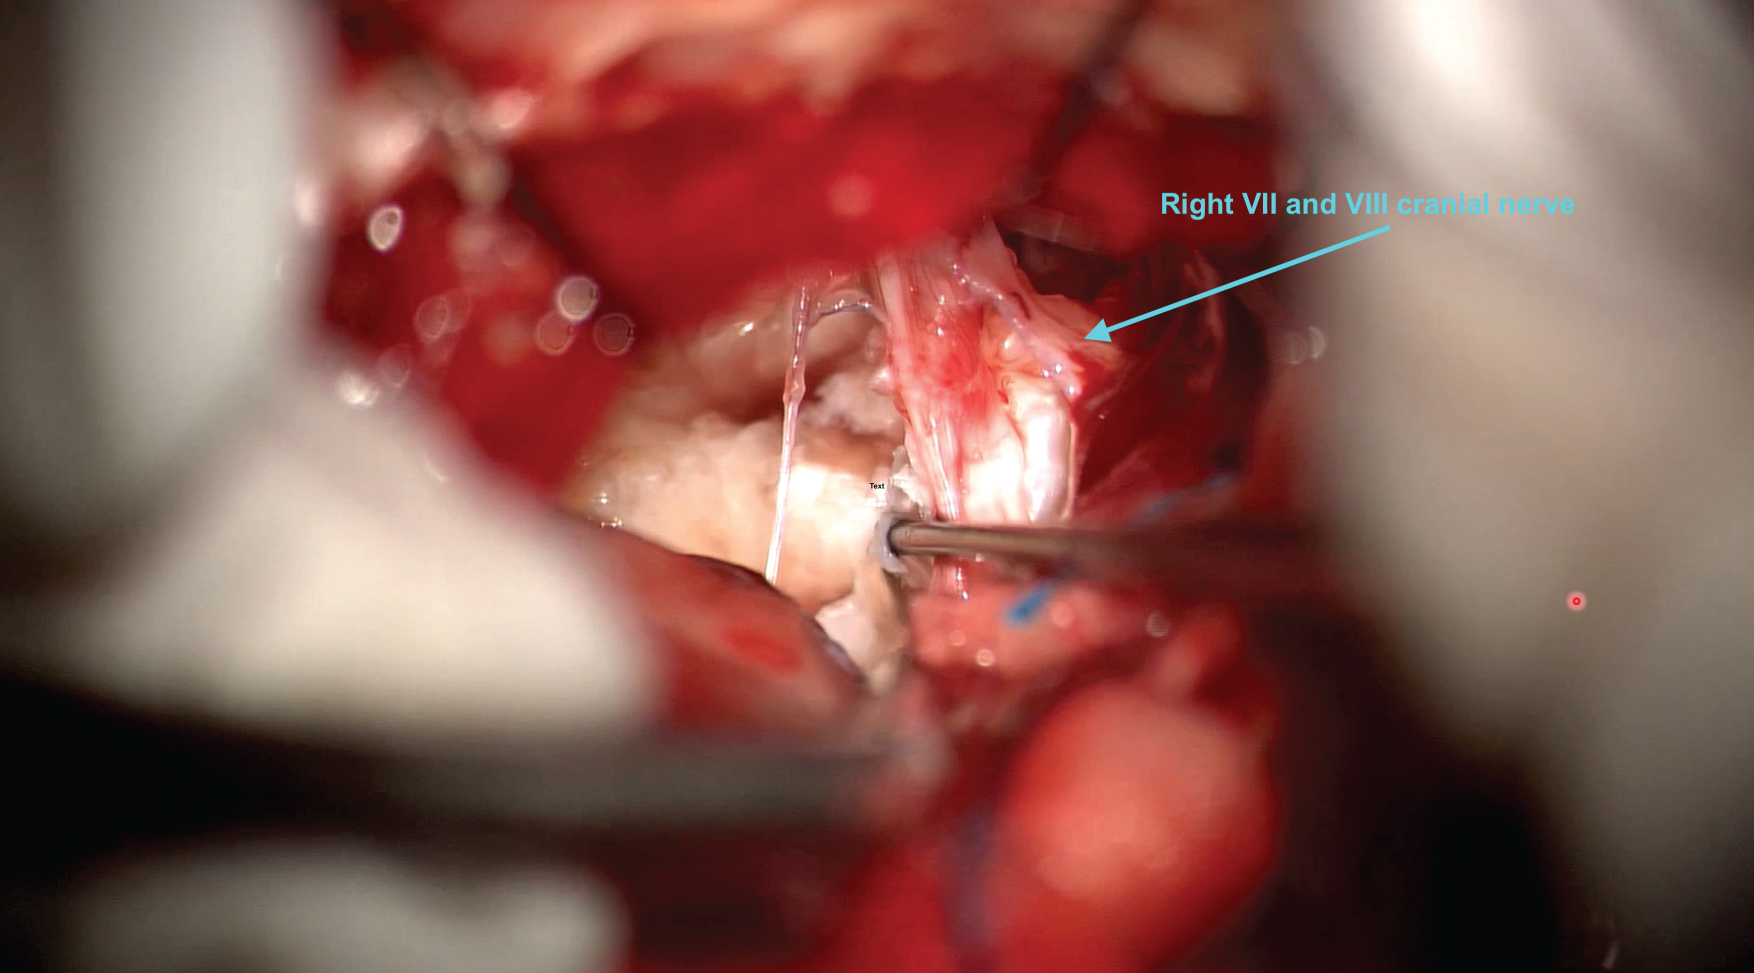

Operation one involved a right sided retrosigmoid craniotomy which was undertaken with neuronavigation and facial nerve monitoring. During this operation the tumour was dissected from the upper, middle and lower neurovascular complexes. The tumour was dissected from both sides of the basilar artery and maximal safe removal of the tumour in the interpeduncular cistern was achieved. Residual was left in this area and in the middle cranial fossa. Reconstruction was completed with a watertight dural closure and copious Ringer’s lavage, refer to Figure 1 and Figure 2. The patient was discharged home with a weaning dose of steroids over 7 days from the date of their operation.

Figure 1: Photograph during the resection phase of the first operation. The view is through a right sided retrosgimoid craniotomy focusing on the middle neurovascular complex of the cerebellopontine angle cistern demonstrating the dissection of the epidermoid tumour off the VIIth and VIIIth nerves. View Figure 1